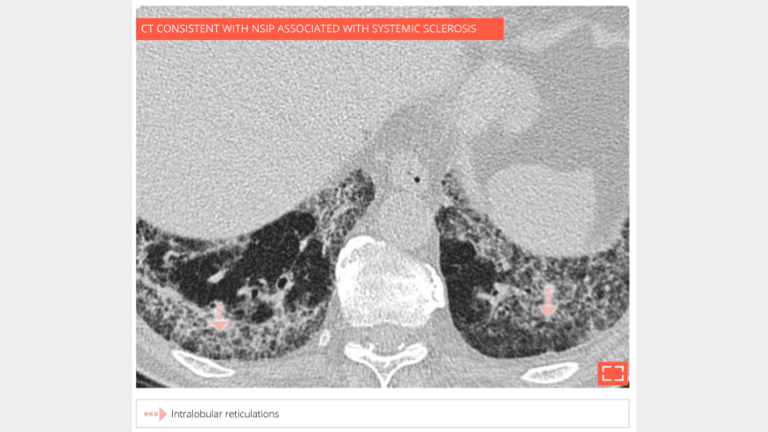

Intralobular reticulations

Marked intralobular reticulations in the 2 lung bases without honeycombing. Note the relative lung savings immediately under pleura, pointing to a NSIP.